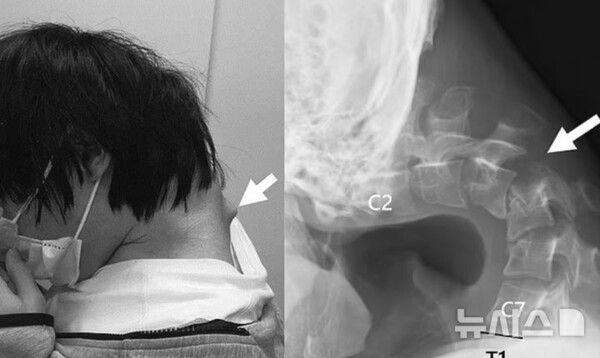

장시간 스마트폰 사용으로 인해 목뼈가 꺾여 고개를 제대로 들 수 없게 된 20대 남성의 사례가 공개됐다.

뉴시스 보도에 따르면, 14일(현지시각) 데일리메일에 따르면, 일본 의료진은 최근 학술지를 통해 스마트폰 과다 사용으로 목뼈가 심하게 손상된 25세 남성의 사례를 소개했다.

해당 남성은 약 6개월간 극심한 목 통증을 겪다 병원을 찾았다.

당시 그는 스스로 고개를 들 수 없는 상태였고, 음식물을 삼키기조차 힘들어 식사량이 현저히 줄면서 체중이 급격히 줄었다.

여러 검사 끝에 의료진은 남성의 목뼈가 심하게 뒤로 젖혀져 있는 상태이며, 일부 목의 척추뼈는 비정상적으로 이탈한 것을 발견했다.

의료진은 이 남성이 수년간 바닥을 보며 스마트폰 게임에 몰두한 결과, 경추에 정상적인 하중이 지속적으로 가해졌다고 판단했다.

특히 목을 깊이 숙인 상태에서 장시간 스마트폰을 사용하는 습관이 원인이 됐다고 의료진은 분석했다.